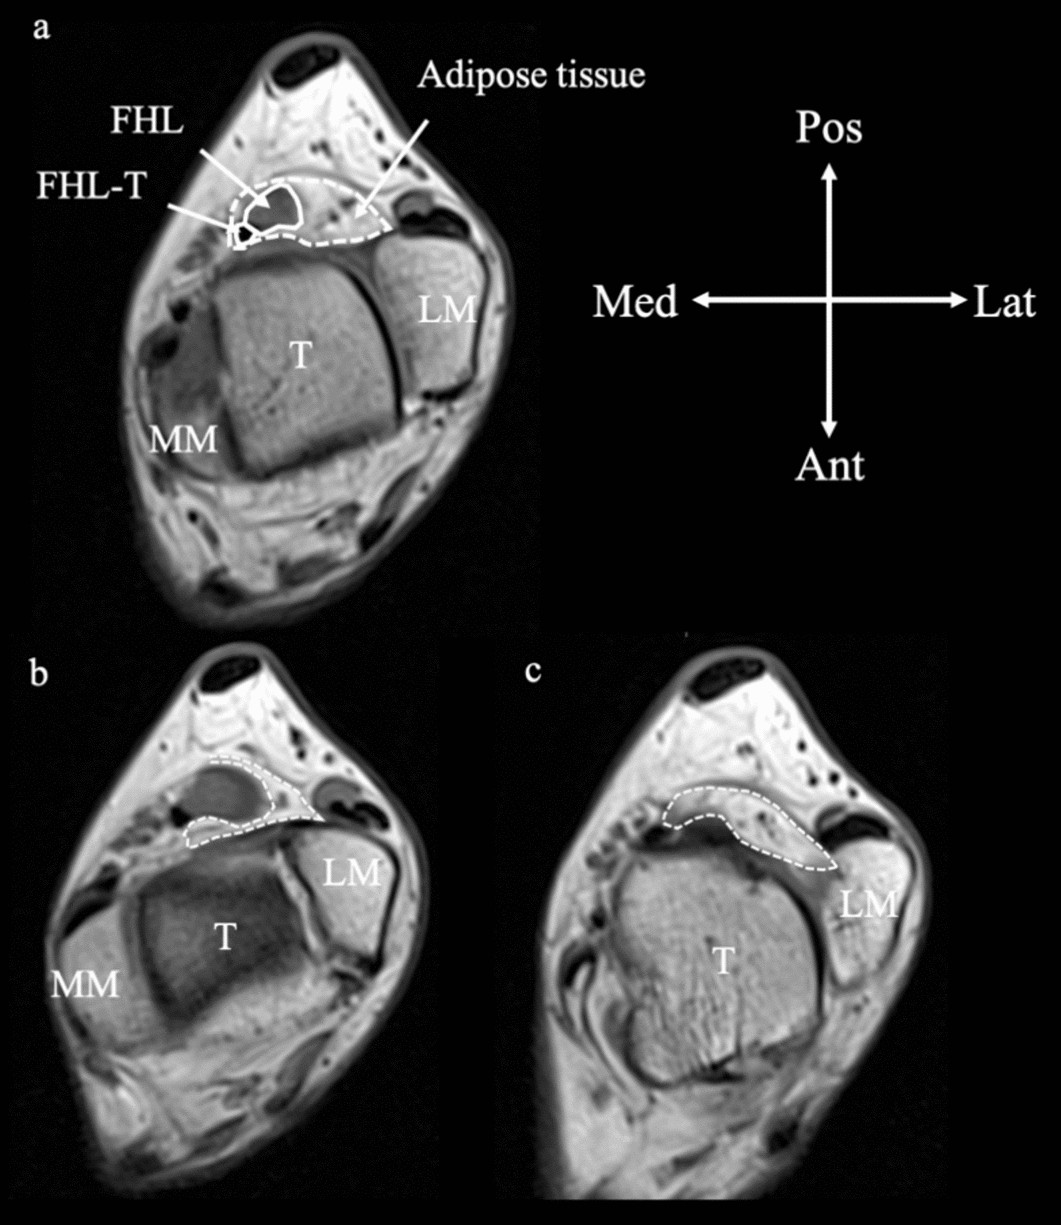

Magnetic resonance image of adipose tissue surrounding the flexor hallucis longus tendon. (a) At the level of the trochlea of the talus. (b) One slice proximal to the trochlea of the talus. (c) One slice distal to the trochlea of the talus. Dotted line: contour of adipose tissue. FHL, flexor hallucis longus; FHL-T, flexor hallucis longus tendon; T, talus; MM, medial malleolus; LM, lateral malleolus; Pos, posterior; Ant, anterior; Lat, lateral; Med, medial.